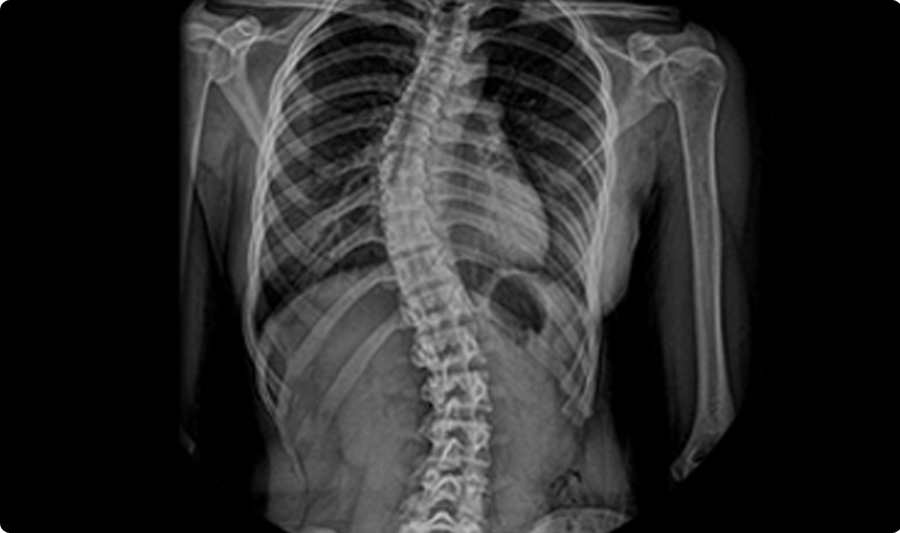

인체의 각 관절, 근육 등의 연부조직이 외부의 충격, 강력한 비틀림, 당김, 압박 및 장기간의 피로 등으로 인해 구조적인 손상을 벋어 통증이 발생합니다. 정상적인 척추는 정면에서 보았을 때 반듯하게 골반위에 있어야 합니다. 그러나 척추가 ‘L자’나 ‘C자’ 모양으로 휘어지고 동시에 척추 마디마디가 회전하여 틀어지는 변형을 함께 동반하기도 하는데, 이러한 척추의 변형을 척추측만증이라고 합니다.